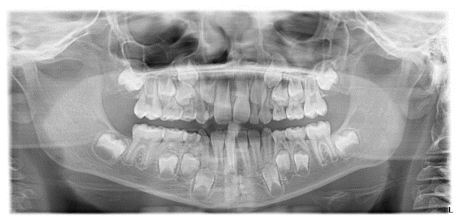

The patient was a 6-year-old female presenting with a Class III dento-skeletal malocclusion associated with anterior crossbite in the early mixed dentition (Figures 20–26). Baseline diagnostic records included orthopantomography, latero-lateral cephalometric radiography with cephalometric analysis, and extraoral and intraoral photographs. Clinical examination revealed a flat-to-slightly convex facial profile with sagittal skeletal discrepancy and negative overjet (Tables 5, 6). The treatment consisted exclusively of functional orthopedic therapy using the AMCOP® TC appliance, worn throughout the night and for one additional hour during the day, for a total duration of 24 months. At the end of active treatment, complete correction of the anterior crossbite was achieved, with normalization of overjet and overbite and establishment of a Class I dental relationship. A long-term follow-up evaluation performed at the age of 12 years, in complete permanent dentition, confirmed the stability of the results, showing a well-maintained anterior dental seal and a stable Class I occlusion. The AMCOP® TC appliance was continued as nighttime retention only, supporting neuromuscular balance and occlusal stability throughout growth.